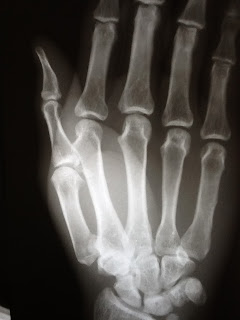

Bennett's fractures, treated with surgery. If you suspect a fracture of any bones in your hand then seek urgent medical attention immediately.

Dr yuranga weerakkody ◉ and r bronson et al. If the shaft of the bone is broken and/or the soft tissues around the. With bennett's fracture, a small part of the metacarpal bone will remain attached to the volar ligament, whilst the main part of the bone is dislocated. Chris morgan connects with iain hume, leaving an. Voluntary clinical professor of orthopedic surgery and plastic surgery, departments of orthopedic surgery and surgery, university of miami. It is an oblique scrapping that passes through the base of the metacarpal bone. Bennett's fracture possesses considerable potential stability. Even following surgery there is a reasonably high risk of long term arthritis of the cmc joint of the thumb. Greater than 1 mm of articular incongruity initially or at follow up after closed reduction is an indication for surgery. The fracture involves the joint surface and is often significantly displaced. The causative mechanism is axial overload along the first metacarpal, combined with simultaneous flexion. Bennett fracture usually occur following a fall onto or impaction injury of the thumb. In 1882, edward hallaran bennett, md, described the fracture of the base of the first metacarpal that bears his name. Bennett's fractures under arthroscopic control. Anatomy, roentgenology, and therapy., gedda ko,, acta chirurgica scandinavica. The specific bone that's affected is the authors caution that more complex fractures may still require an open surgery. If adequate reduction cannot be achieved by means of this percutaneous technique, open reduction and internal fixation (orif) is.